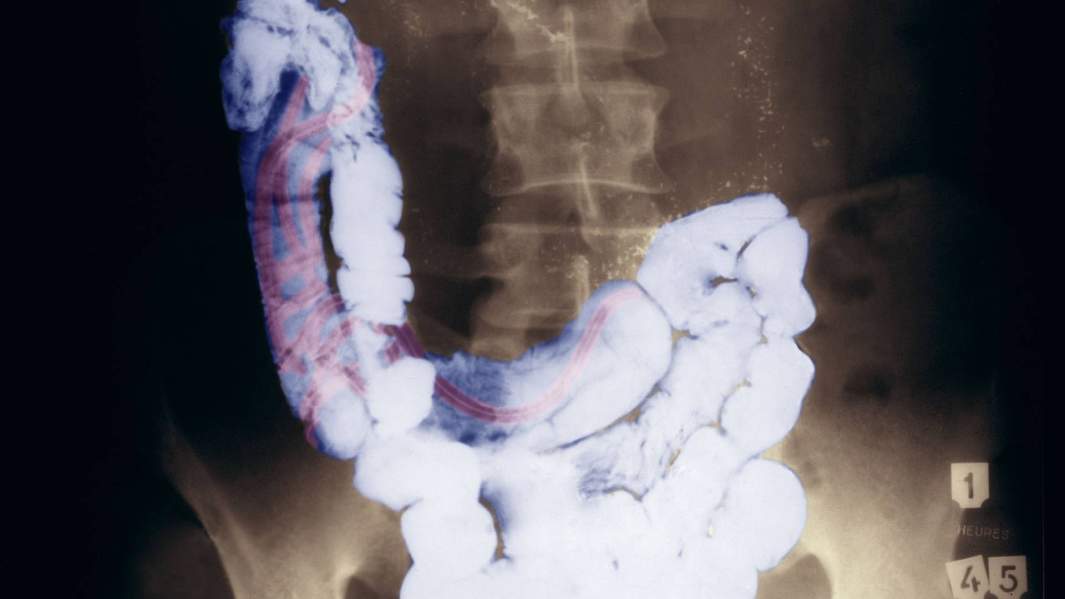

Ученые рассказали «Известиям», почему люди, зараженные глистами и другими кишечными паразитами, зачастую переносят коронавирус в легкой форме. Поводом стала публикация в научном журнале The Lancet, в которой авторы изучили статистику заражений в Эфиопии и выяснили: у людей с паразитами редко бывает тяжелая форма заболевания. Как пояснили российские эксперты, при COVID-19 в патогенезе ведущую роль играют провоспалительные цитокины, которые и вызывают цитокиновый шторм. А гельминты способны изменять иммунный ответ и убирать эффект гипервоспаления, чтобы выжить внутри человеческого тела. Открытие этого механизма и его детальное исследование могут помочь разработать эффективное терапевтическое средство.

Коинфекция (сопутствующее заболевание) кишечными паразитами может быть одним из объяснений того, почему одни люди болеют СOVID-19 легко, а другие нет. Это подтверждают данные, недавно опубликованные в научном журнале The Lancet. Специалисты из колледжа медицинских наук Университета Мекелле в Эфиопии задумались над вопросом, почему в Африке значительно меньше пациентов страдают от серьезных симптомов COVID-19, чем в промышленно развитом мире.

«Мы предполагаем, что частичное объяснение этого явления заключается в большей активации иммунной системы жителей Африки, вызванной паразитарными инфекциями», — указано в статье. Чтобы проверить эту гипотезу, с июля 2020 года по март 2021-го авторы исследовали данные пациентов с COVID-19, которые прошли скрининг на кишечных паразитов. Всего в выборку включили 751 пациента, инфицированных SARS-CoV-2, из которых 284 (37,8%) были заражены гельминтами (глистами) или простейшими паразитами.

У пациентов, коинфицированных паразитами, тяжелая форма COVID-19 развилась лишь в 10% случаев. При этом больше половины (51,8%) заболевших, зараженных паразитарной инфекцией, перенесли коронавирус в легкой форме. Реже всего осложнения появлялись у людей, зараженных Entamoeba spp (заражение дизентерийной амебой), Hymenolepis nana (карликовым цепнем), Schistosoma mansoni (кровяным сосальщиком — вид плоских червей) и Trichuris trichiura (заражение червем — власоглавом).

Ученые их Эфиопии пришли к выводу, что иммуномодулирующие реакции, вызванные паразитами, могут заглушить гипервоспаление, связанное с тяжелой формой COVID-19.